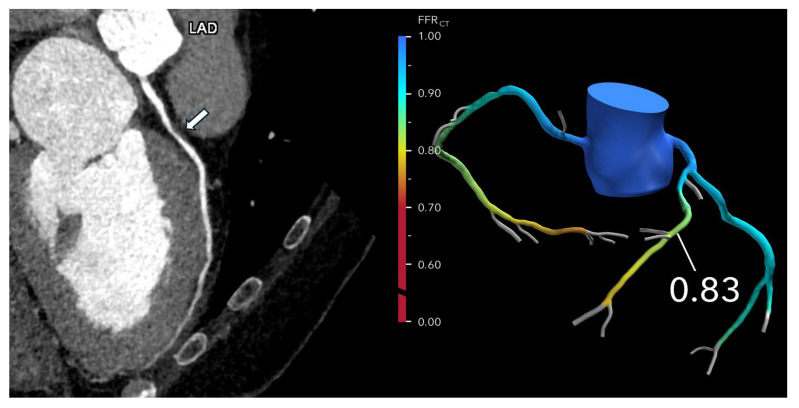

Coronary computed tomography angiography (CCTA) has emerged as the leading noninvasive imaging modality for the assessment of coronary artery disease (CAD), offering high-resolution visualization of the coronary anatomy and plaque characterization. The development of fractional flow reserve derived from CCTA (FFR-CT) has further transformed the diagnostic landscape by enabling the simultaneous evaluation of both anatomical stenosis and lesion-specific ischemia. FFR-CT has demonstrated diagnostic accuracy comparable to invasive FFR. The combined use of CCTA and FFR-CT is now pivotal in a broad range of clinical scenarios, including the evaluation of stable and acute chest pain, assessment of high-risk and complex plaque features, and preoperative planning. As evidence continues to mount, CCTA and FFR-CT are positioned to become the primary gatekeepers to the cardiac catheterization laboratory, potentially reducing the number of unnecessary invasive procedures. This review highlights the growing clinical utility of FFR-CT, its integration with advanced plaque imaging, and the future potential of these technologies in redefining the management of CAD, while also acknowledging current limitations, including image quality requirements, cost, and access.